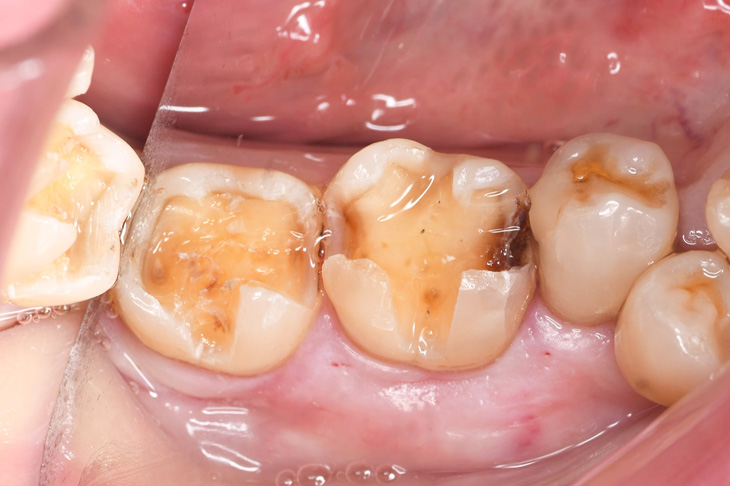

右下奥歯のセラミックインレー

Before

途中経過

After

基本情報

| 年齢・性別 | 50代・女性 |

|---|---|

| 主訴 | 銀歯を白くしたい 右下67 |

| 治療内容 | 右下67セラミックインレー |

| 治療費 | 110,000円 (セラミックインレー1本55,000円) |

| 治療期間 | 約1~2週間 |

| リスク・副作用 | 稀に割れることがある 凍みることがある 再度虫歯になる可能性がある |